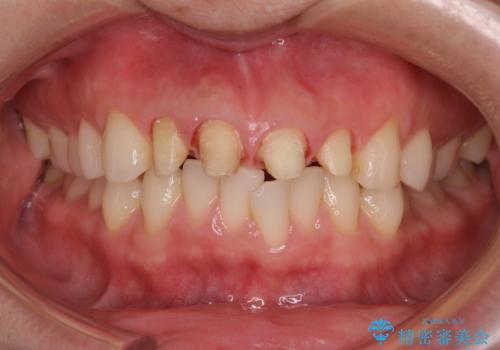

- 以前他院で治療を行った前歯の被せものが欠けてしまい、きれいなセラミックにしたいと来院された患者様です。

人工物のような印象が強くあまり自然とは言えない状態でした。

また被せものと土台の間に隙間があり、適合もよくない状態でした。

根管治療のやり直しは希望されなかったため、土台のやり替えと、より自然なオールセラミッククラウンへのやり替えを行いました。